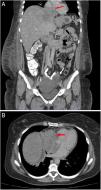

A 45-year-old female with no past medical history presented to the hospital with six months of dry cough, associated with diffuse abdominal pain and lower extremity edema. On physical examination, grade two lower extremity edema and ascites were found. The results of the laboratory tests demonstrated elevated Ca-125. Abdominal tomography was performed showing left complex adnexal mass and lobulated hepatic mass with compression and displacement of inferior vena cava and right atrial extension (Figure 1A and 1B). Transthoracic echocardiography documented echo-dense mass of 32 mm×31 mm, area 9.8 cm2, suggestive of intracavitary right atrial thrombus (Figure 2A, 2B and 2C, Video 1A-1C in supplemental material), left ventricular ejection fraction and diastolic function were normal and the valves had no pathologic changes. Cardiac magnetic resonance was not performed. Additionally, Holter electrocardiogram recorded atrial tachycardia. Anticoagulation was initiated. Left oophorectomy was performed based on results of diagnosis of serous ovarian carcinoma. Liver, neck and bone metastatic disease was observed. Chemotherapy with carboplatin and paclitaxel was started. Currently, patient is receiving the second cycle of chemotherapy, symptoms have been relieved without cardiovascular events. Control images will be performed after chemotherapy has been completed to assess therapy response.

A: Coronal thoracic computed tomography showing left complex adnexal mass (white arrow) and lobulated hepatic mass with compression and displacement of inferior vena cava and right atrial extension (red arrow). B: Axial thoracic computed tomography showing mass with right atrial extension (red arrow).